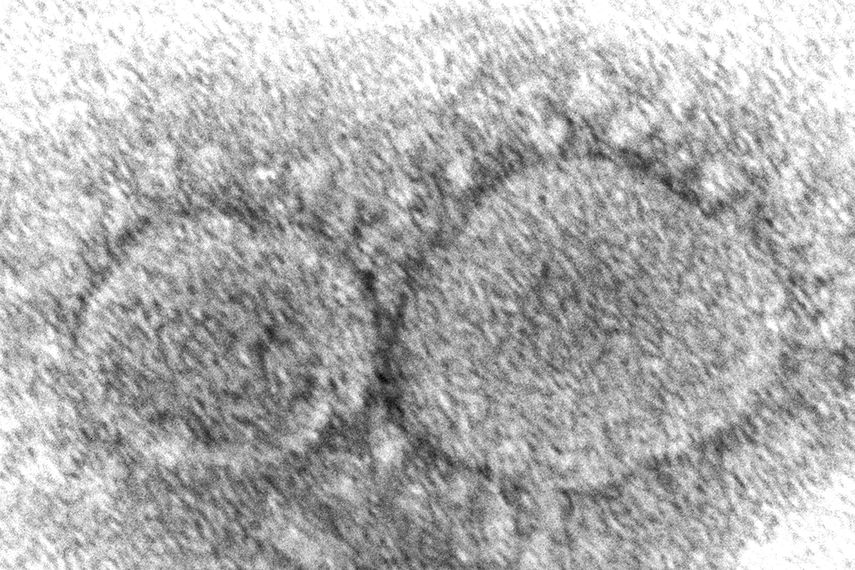

La versión de coronavirus que se ha vuelto la más dominante en Estados Unidos pertenece a la familia ómicron, pero los científicos aseguran que se propaga más rápido que sus predecesoras, es capaz de eludir a la inmunidad y posiblemente puede causar un cuadro más grave.